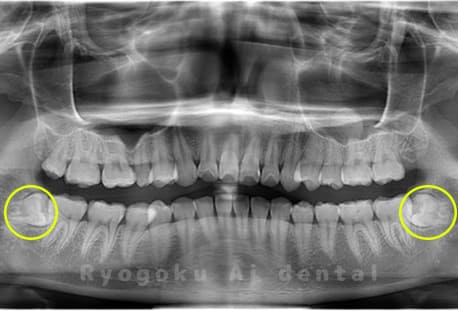

Case15

- 下顎左右2本の親知らず

- 治療内容

- 下顎左右2本の親知らずを抜歯したケースです。

<リスク・副作用>

手術後は痛み、腫れ、痺れなどの副作用が生じる場合があります。